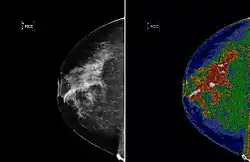

A region of interest (often abbreviated ROI), are samples within a data set identified for a particular purpose.[1] The concept of a ROI is commonly used in many application areas. For example, in medical imaging, the boundaries of a tumor may be defined on an image or in a volume, for the purpose of measuring its size. The endocardial border may be defined on an image, perhaps during different phases of the cardiac cycle, for example, end-systole and end-diastole, for the purpose of assessing cardiac function. In geographical information systems (GIS), a ROI can be taken literally as a polygonal selection from a 2D map. In computer vision and optical character recognition, the ROI defines the borders of an object under consideration. In many applications, symbolic (textual) labels are added to a ROI, to describe its content in a compact manner. Within a ROI may lie individual points of interest (POIs).

Examples of regions of interest

- 2D dataset: the boundaries of an object on an image